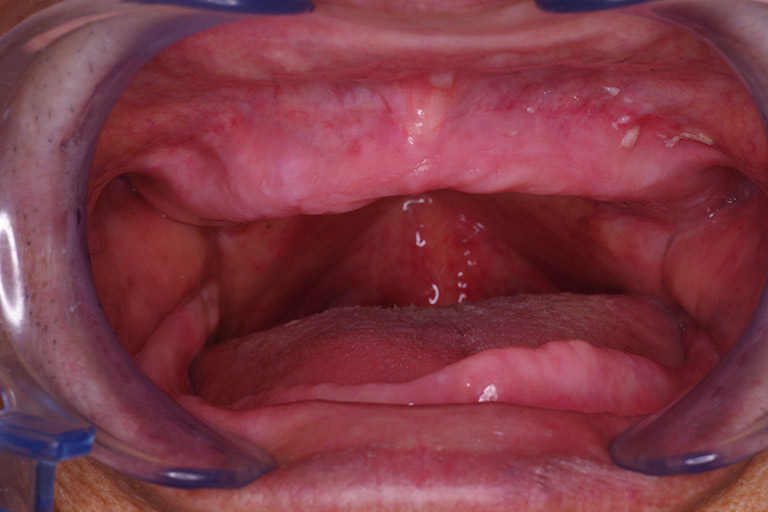

白板症

白板症は舌や歯肉、頬粘膜などに生じる白色の病変です。前がん病変とも言われ、がん化することもあります。

治療法

白板症は悪性ではないため経過観察することが多いです。しかし、前がん病変のため、病変の一部を採取して病理検査を行う生検を行い、病理診断しておく必要があります。病変の大きさや、程度によっては、全てを切除する切除生検を行うこともあります。

扁平苔癬

扁平苔癬は口腔粘膜に生じる角化を伴う炎症性病変です。レース状の白斑を呈するのが特徴です。原因は不明ですが、金属アレルギーとの関連も言われています。

口腔カンジダ症

口腔粘膜にカンジダ(真菌;カビ)により白苔が生じたり赤くなったり生じます。カンジダは口腔内に常にいる真菌ですが、免疫力の低下や抗菌薬の投与などで生じる日和見感染で発症します。